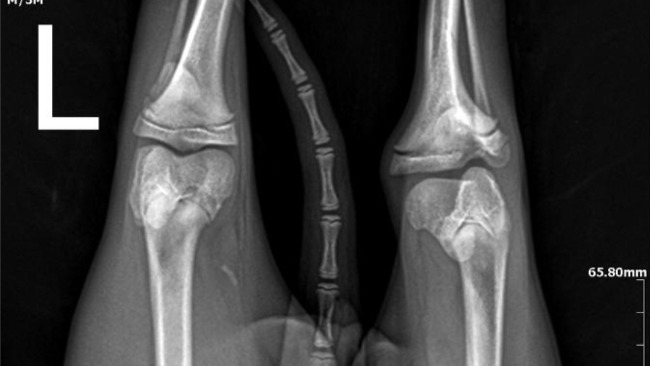

Zostałam zabrana od niedobrego Pana, który trzymał mnie w klatce i nie traktował dobrze. Urodziłam się z przesunięta rzepką, a poprzez nie odpowiednie traktowanie mnie doprowadziła do atrofii mięśni mojej łapki co spowodowało dysplazje moich bioderek.